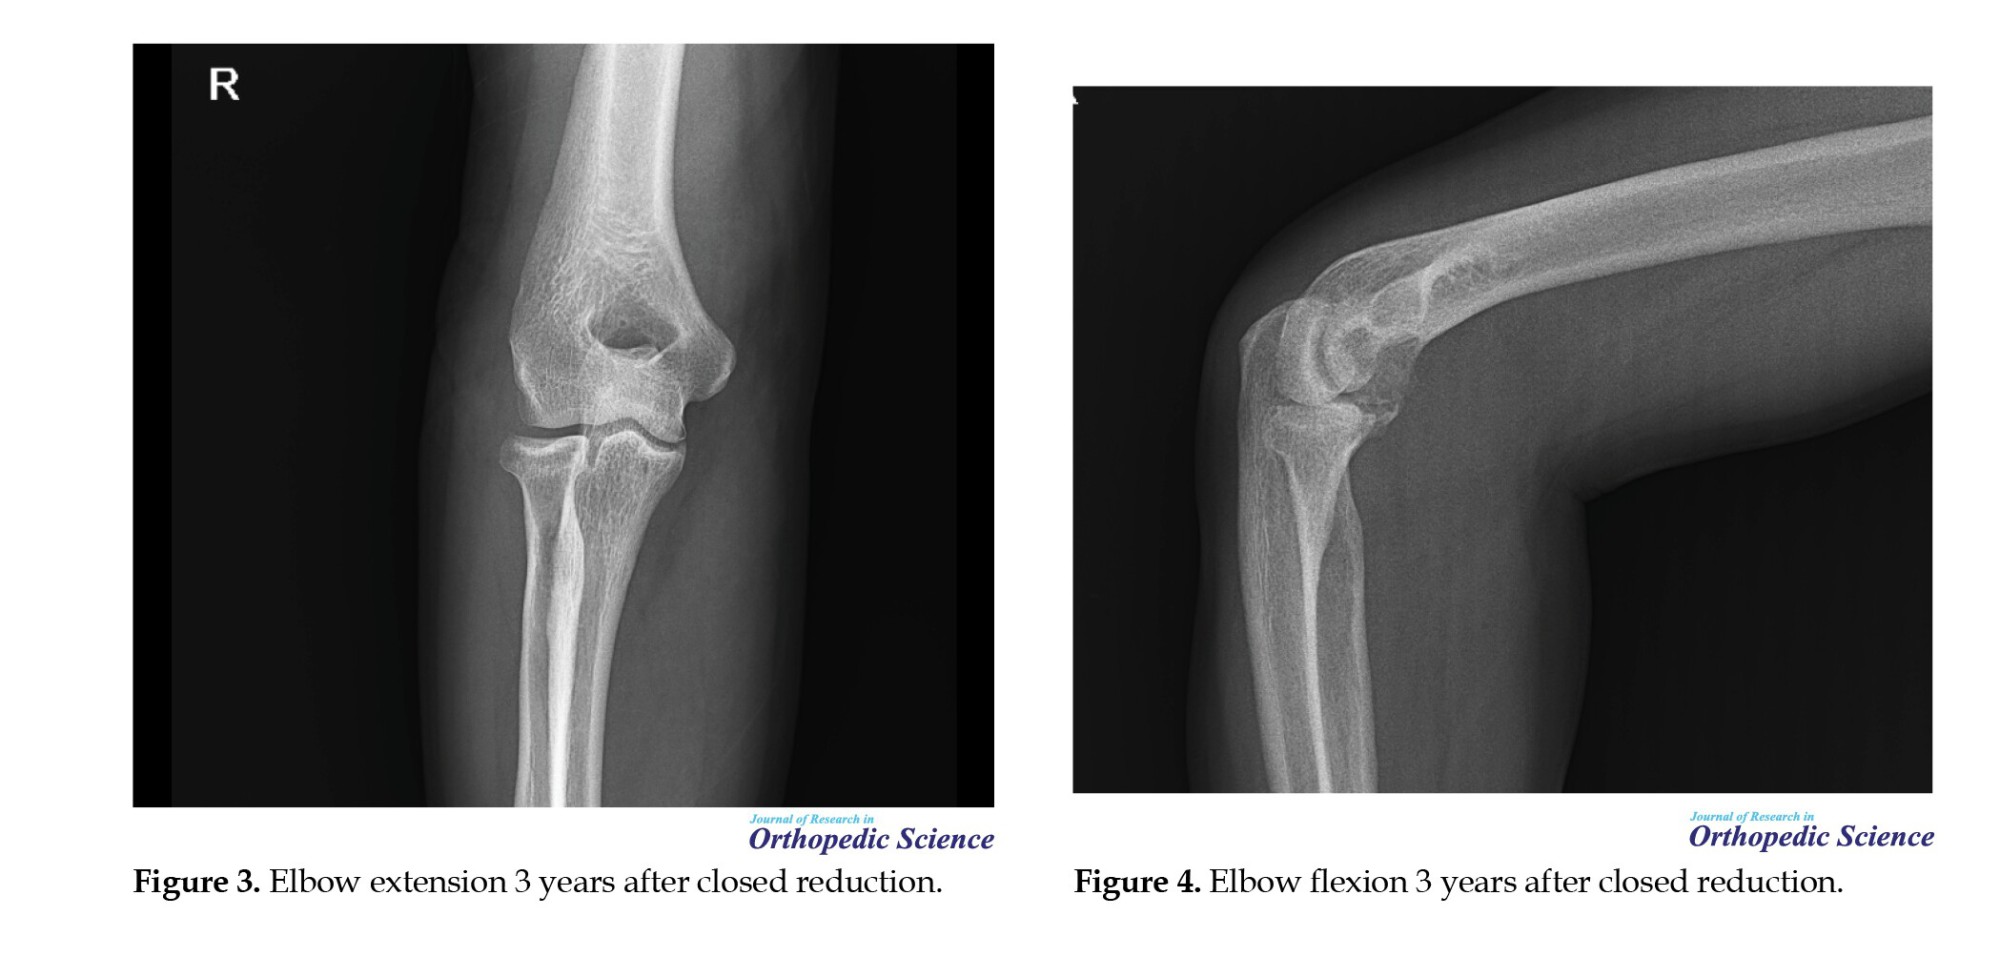

All patients underwent closed reduction under conscious sedation in the operating room. Post-reduction radiographs and CT scans were obtained to confirm joint congruency and assess fracture patterns (Figures 1 and 2).

Patients were referred to physiotherapy for early active ROM exercises, with extension initially limited to 45 degrees and gradually increased weekly. Functional outcomes were assessed using the Mayo elbow performance index (MEPI) and the disabilities of the arm, shoulder, and hand (DASH) score. ROM was measured using a goniometer, and radiographic evaluation was performed to determine joint congruency, fracture :union:, and the presence of arthritis (Figures 3, 4, 5 and 6).